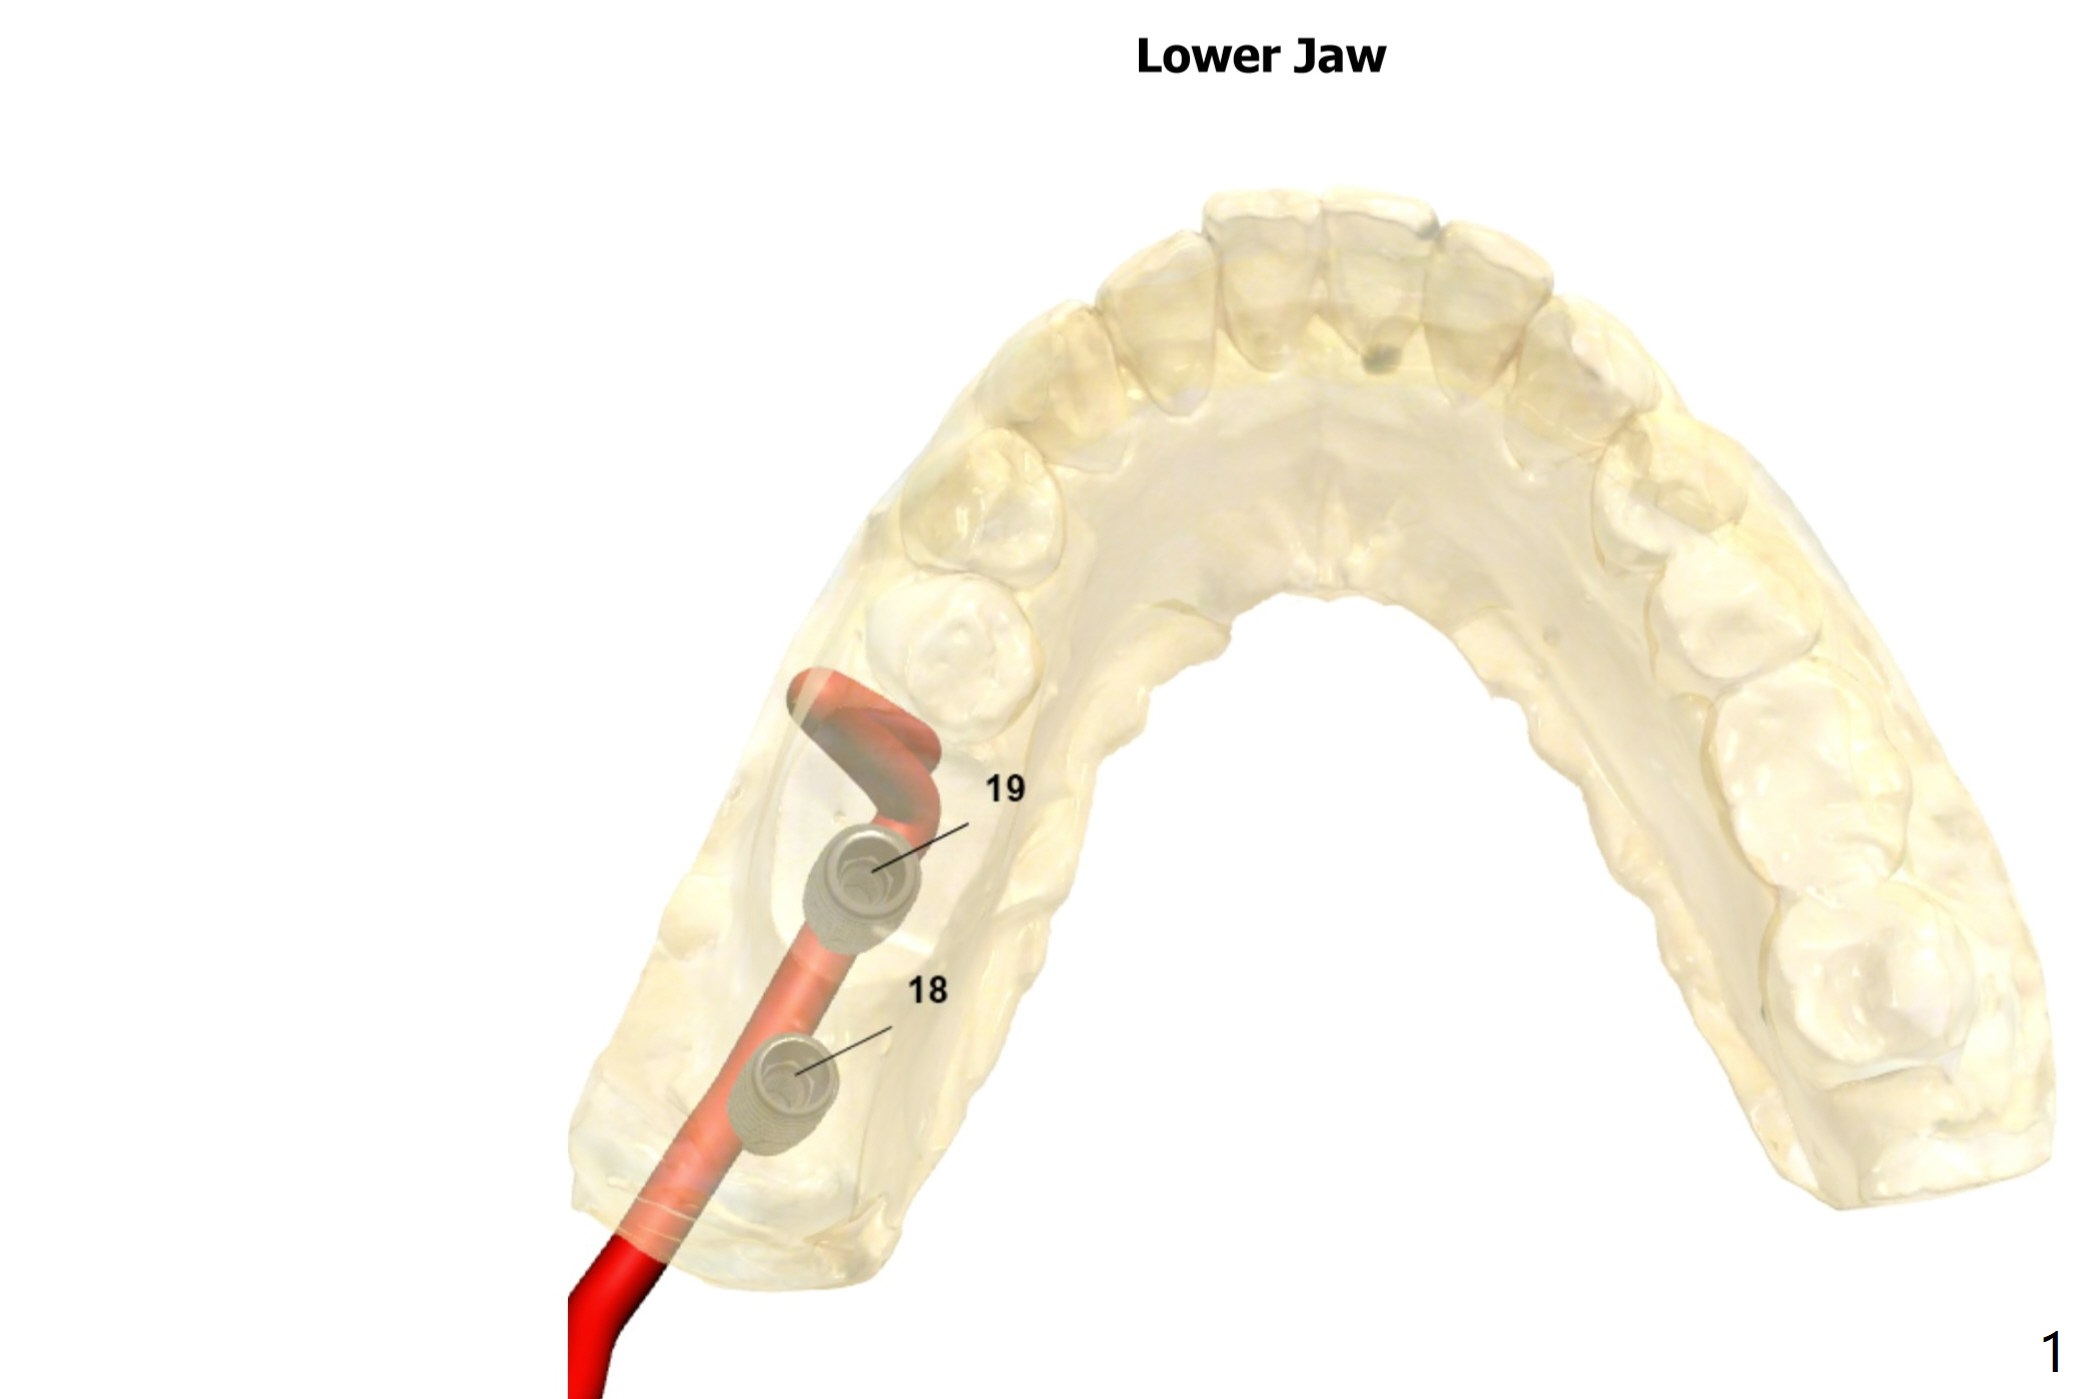

Limited Vertical Space

Return to Lower Molar Immediate Implant, Trajectory II